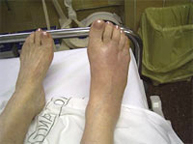

The foot region is a set of bones and joints with many features among which support our weight and ambulation (walking). The foot in turn is divided into three parts: the hindfoot, midfoot and forefoot. Every region suffers from its peculiar injuries. In sport foot injuries are common due to the involvement of it in most of them. Usually foot fractures respond well to conservative treatment reserving the surgical approach to those complex irreparable injuries in the hindfoot.